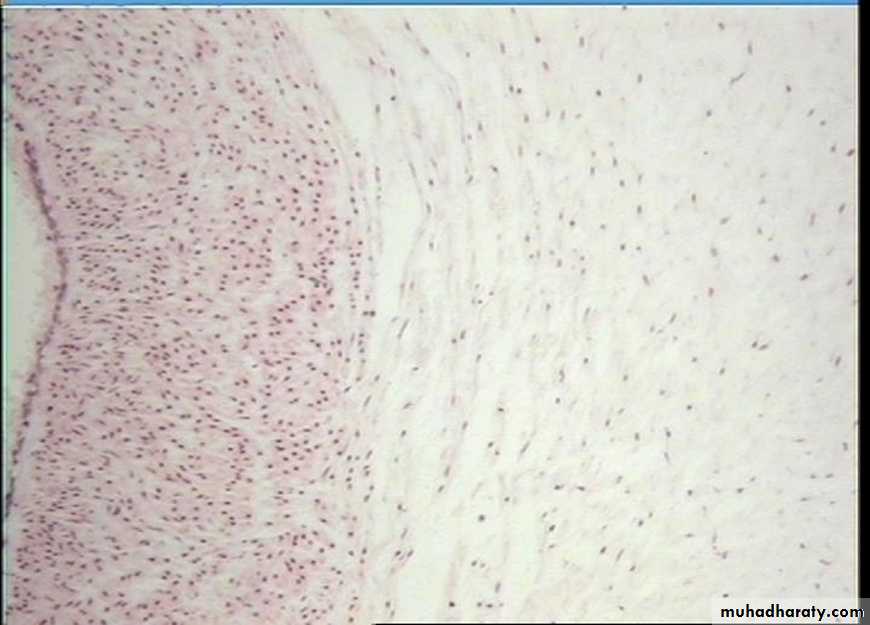

contains thicker and densely packed collagen fibers (fewer cells-types and less ground substance),• irregular dense connective tissue exhibits a random and irregular orientation of its collagen fibers, it is present in the dermis of skin, in capsule of different organs, and in areas for strong support.

• Regular Dense connective tissue exhibits densely packed collagen fibers with regular and parallel arrangement. This type of tissue is found in the tendons and ligaments Fig (5).